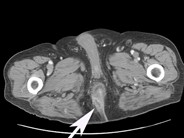

A 42-year-old male with history of myelodysplastic syndrome with progression to acute myeloid leukemia, which relapsed after induction therapy, was admitted to the hospital for initiation of Clofarabine therapy to reduce disease burden prior to bone marrow transplantation. On admission his white cell count (WBC) was 5200/uL with 77% blast cells and absolute neutrophil count(ANC) of 104/uL. Day 2, after chemotherapy, he was febrile and his WBC was 0/uL. He was empirically started on imipenem, daptomycin and amphotericin. Day 4, he developed erythematous lesion on abdomen(Fig.A) and right big toe(Fig.B). Computed tomography showed bibasilar pulmonary and hepatosplenic lesions (Fig C&D). The abdominal skin lesion developed a necrotic center with erythematous halo. All cultures were negative but KOH preparation from skin lesion showed nonseptate hyphae. Skin punch biopsy results were suggestive of mucormycosis. Patient was presumed to have disseminated mucormycosis. He failed to respond to dual antifungal therapy of high dose amphotericin and caspofungin. Disseminated mucormycosis is a rare and mostly fatal complication in severely immunocompromised patients.